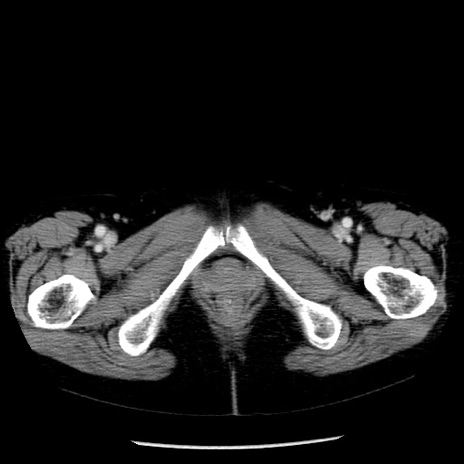

症例13(横断像)

【症例】70歳代女性

【主訴】腹痛、嘔吐

【現病歴】15時間程前(昨晩)より腹痛あり。今朝になっても症状の改善なく、嘔吐あり。腹痛も増悪あり、救急外来受診。

【既往歴】子宮癌全摘術後

【身体所見】意識清明、BP 121/72mmHg、P 74bpm、SpO2 100%(RA)、腹部:平坦・軟、腸雑音ほぼ聴取せず。下腹部・心窩部・臍左上に圧痛あり。反跳痛なし。

【データ】WBC 10600、CRP 0.15